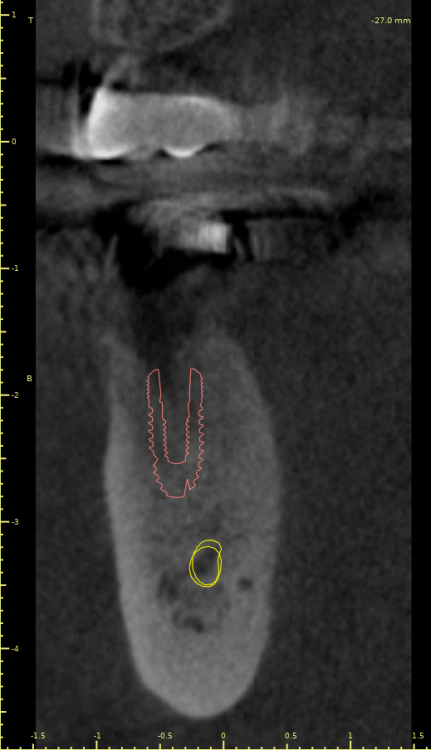

Коллеги, во время пилотного сверления как в области 4.5 так и в области 4.7 пациент отметил резкую боль. Если покрутить КТ, то как раз в местах планируемых имплантатов есть небольшие костные дефекты (хотя конечно на дефект это не тянет, тогда как называть?).

И у 4.5